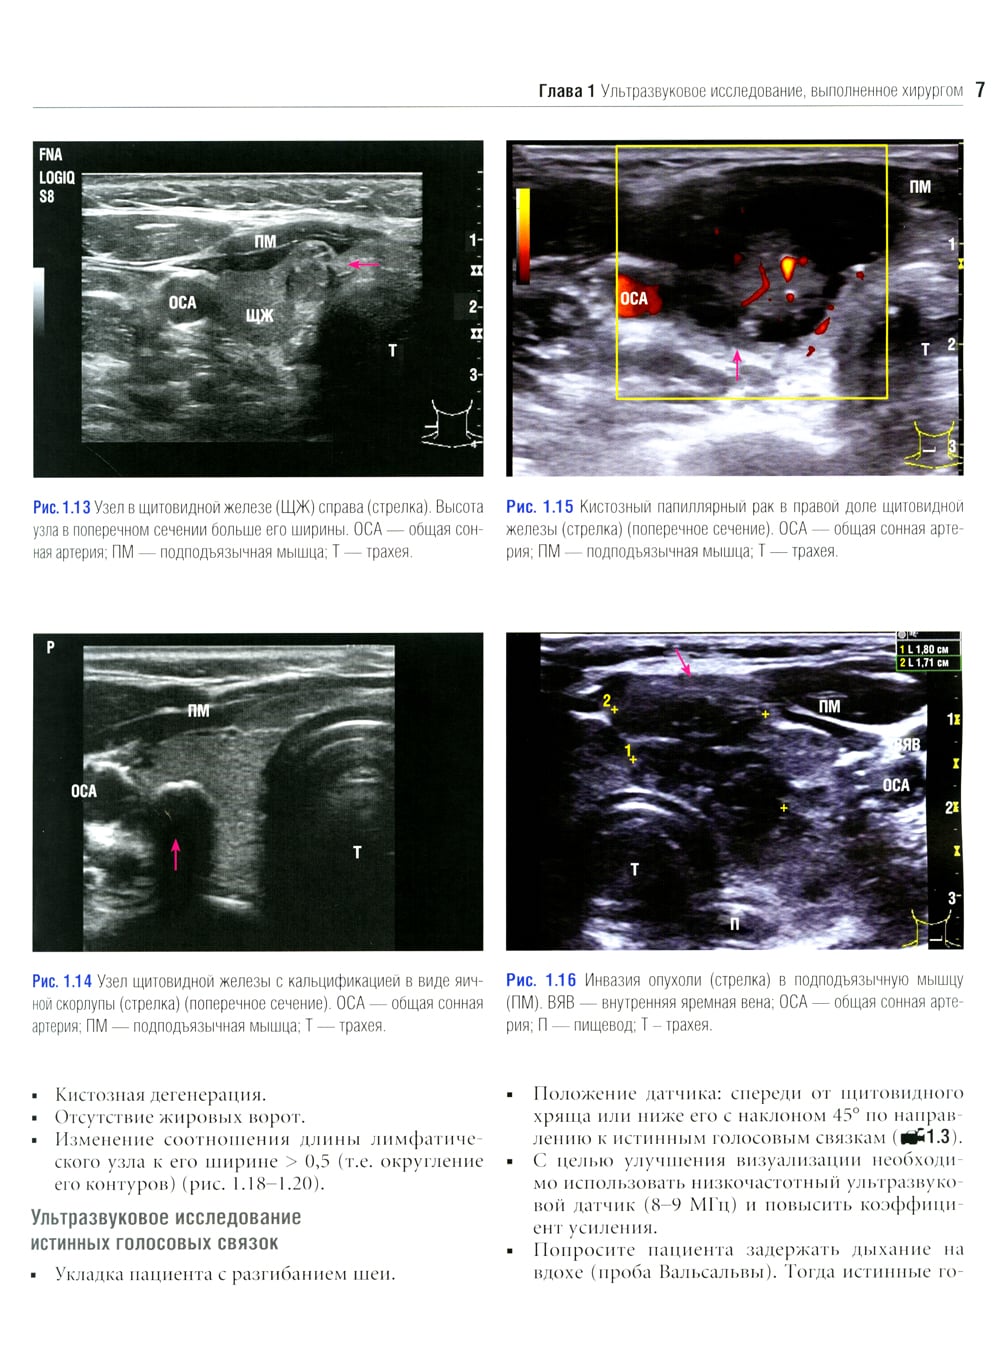

Данное издание представляет собой великолепно иллюстрированный хирургический атлас. В нем рассмотрены методы ультразвукового исследования шеи, молекулярно-генетическое тестирование пациентов с узловыми образованиями в щитовидной железе, робот-ассистированные хирургические методы, техника эндоскопических операций при эндокринных опухолях, хирургия при рецидиве заболевания, аутотранснлантация и криоконсервация околощитовидных желез, адреналэктомия при метастазе в надпочечнике, хирургия нейроэндокринных опухолей тонкой кишки и их метастазов в печени. «Атлас эндокринной хирургии» состоит из 4 частей: «Хирургия щитовидной железы», «Хирургия околощитовидных желез», «Хирургия надпочечников», «Хирургия опухолей поджелудочной железы и карциноидов». Всего в издании 29 глав, подготовленных сотрудниками экспертных факультетов ведущих медицинских школ США, Европы и Азии. Каждая глава состоит из разделов, в которых описаны общие сведения, показания и противопоказания, оценка риска, алгоритм принятия решений и планирование вмешательства, необходимое оборудование и материалы, хирургические техники, результаты лечения, осложнения и последующее наблюдение, а также даны советы и предостережения авторов. В книге много информации, которой нет в других источниках. Наряду с многочисленными фотографиями, сделанными в ходе операций, а также данными, полученными при различных методах визуализации, приведено значительное количество иллюстраций и видеоматериалов, демонстрирующих хирургическую технику или обследование. Издание предназначено практикующим врачам в области эндокринной хирургии, специалистам в смежных областях медицины и студентам медицинских высших учебных заведений.| Издательство | Логосфера |